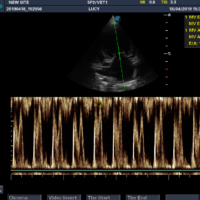

Lucy s-a prezentat la cabinet cu inapetenta, durere abdominala, abdomen destins. Starea ei s-a agravat de 3 zile treptat. Am efectuat palparea abdomenului, unde s-a simtit o masa dura . La ecografia abdominala s-au evidentiat trompele uterine pline cu lichid. Diagnosticul este Piometru cu cervix inchis. Din cauza varstei si a stadiului avansat al bolii, riscurile operatorii cresc, prin urmare se impun efectuarea de investigatii suplimentare. La examenul biochimic ficatul si rinichiul functioneaza in parametri optimi. La auscultatia cordului se aude un suflu de grad III – IV atat pe partea stanga cat si pe dreapta. Se efectueaza EKG si Ecografie cardiaca. La ecografia cardiaca se observa Atriul stang marit cu jet sever de regurgitare, Ventricul Stang hiperkinetic usor dilatat. Se decide sustinerea cardiaca si vasculara periferica si amanarea interventiei cu 24 h. Cand pacientul este stabil si sustinut cardiovascular pentru interventie se efectueaza anestezia. Optam pentru anestezie inhalatorie cu izofluran, protocol specific pentru  pacienti geriatrici. Interventia decurge normal, pacientul este monitorizat, stabil. Postoperator se trezeste rapid, iar dupa 7 zile de medicatie isi revine clinic complet. Ramane pe tratament medicamentos de sustinere cardiaca, boala valvei mitrale fiind o boala progresiva. Se reevalueaza la 6 luni.